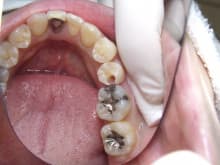

むし歯・

噛み合わせ治療